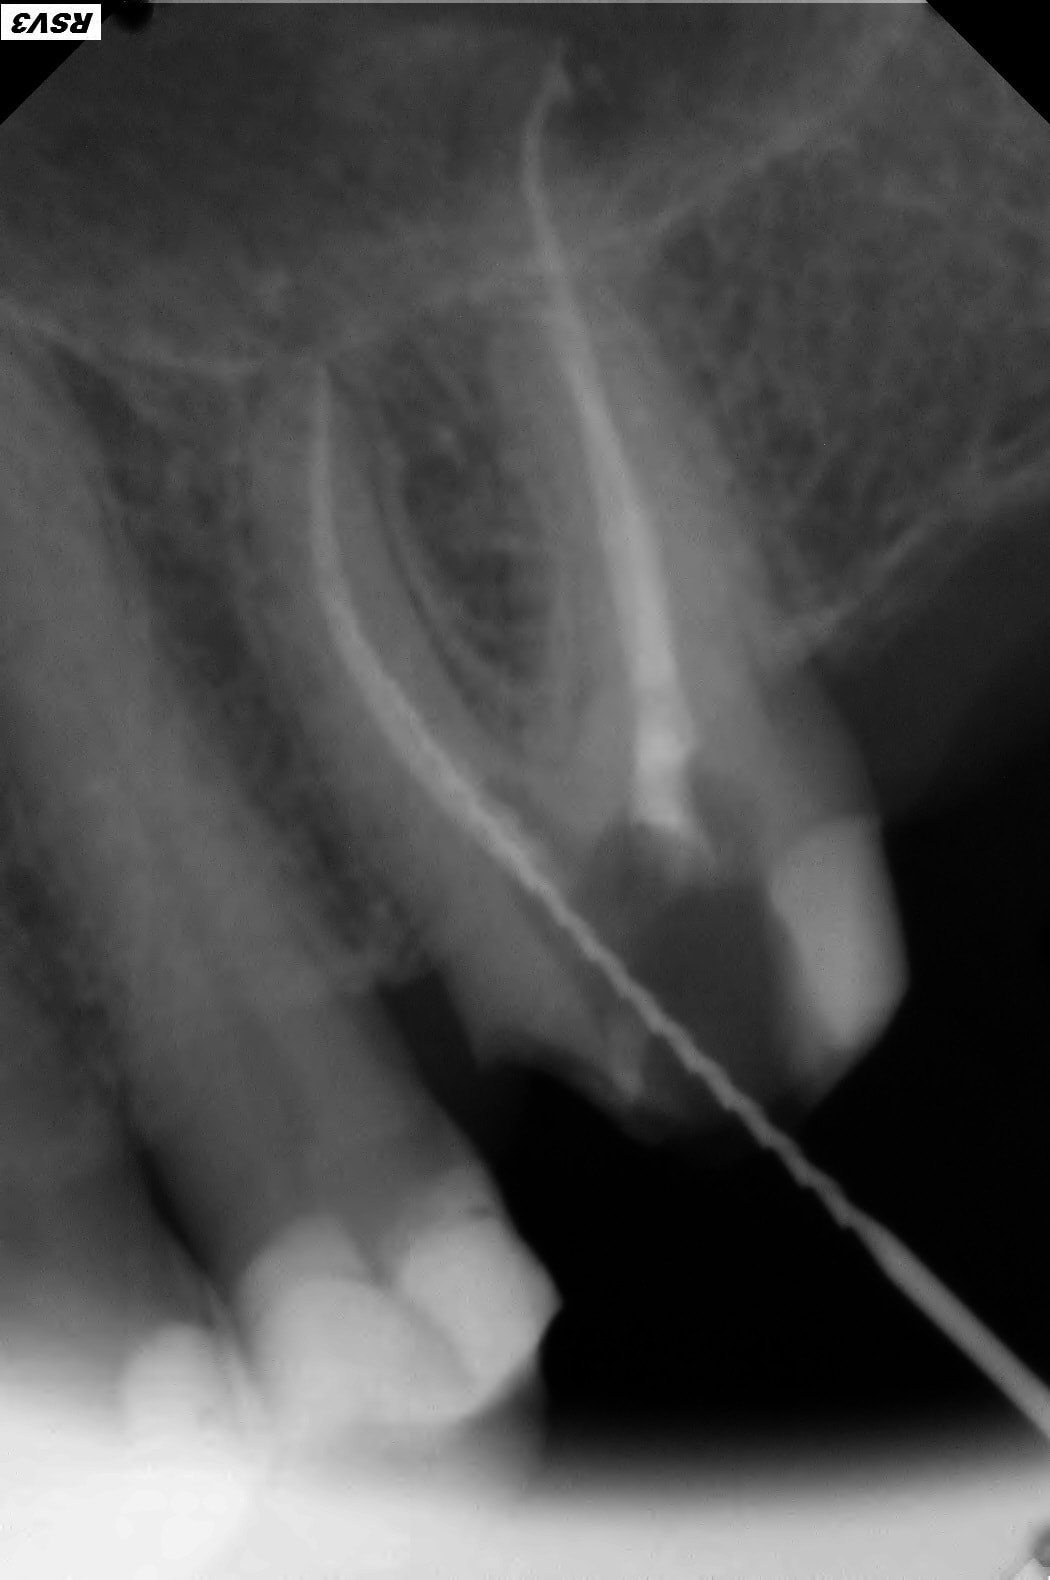

J'ai fait un conebeam de la 26.

L'obturation des racines est correcte, il y a juste une petite image apicale au niveau de la racine palatine avec un léger dépassement de pâte.

Cherche quand même un MV2, tu as les coupes transversales?

Pas de coupes horizontales ?

Le MV2 non obturé ici peut parfois, selon sa configuration, causer des douleurs variées.

Je peux me tromper, les coupes ne sont pas idéales pour conclure ☝️

Pour répondre à Dentarue: je viens de faire des coupes horizontale et centrées sur la racine vestibulaire en tournant autour d'un potentiel MV2. La gutta et le ciment font un joli artefact radio donc ce n'est pas concluant.